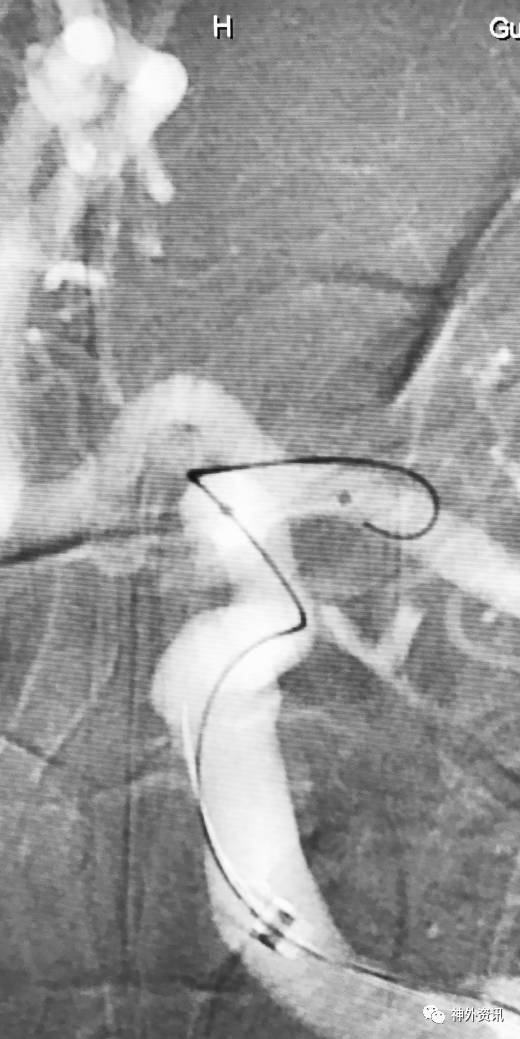

大C塑形

10mm以上的大动脉瘤:

(1)C型头端完全进入动脉瘤囊内,微导管的盘旋有利于均匀填塞

(2)避免微导管头端过早踢出

病例一